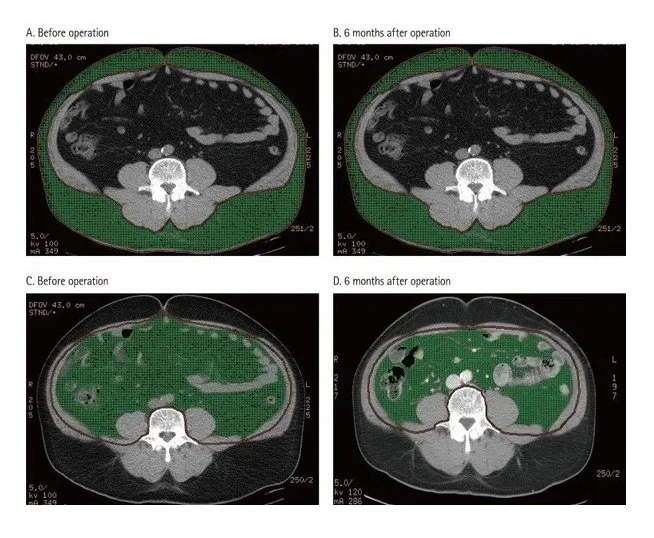

This shows just how fast Visceral Fat is eliminated by simply cutting out PROCESSED FOODS from your diet! In this case series this 68-year-old male client just eliminated processed foods and nothing else, turning from a belly bulging 68-year-old to having a waist/abdomen like a collegiate athlete in their twenties. He did NOT exercise ONE MINUTE. Honestly, you are likely wasting your precious time exercising if you are continuing to eat processed foods. I scan clients to show what really matters - their visceral fat! After showing them their own visceral fat, I provide every client with over 40 strategies to eliminate it and with it their chronic disease.

This MRI scan on the left shows a large amount of pericardial fat in the same 68-year-old business executive and how much it was reduced in the scan on the right in just 13 weeks from simply eliminating processed foods and again without exercising one minute -its diet that matters the most. How much fat do you have around your heart? Pericardial fat almost always correlates with visceral fat. When one is eliminated the other improves.